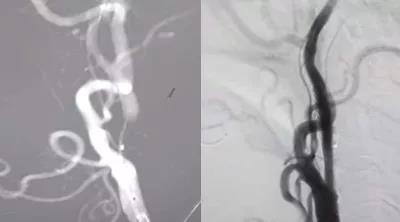

10月27日,在局部麻醉下行介入再通治療,腦血管造影示左側頸內動脈起始處閉塞,微導絲攜1.5*2mm球囊多次嘗試,成功通過閉塞段,給予球囊擴張,擴張后造影見有細血流通過,保護傘緩慢通過狹窄段,釋放保護傘,給予4*20mm球囊再次擴張,然后植入閉環支架一枚,造影示血流通暢,顱內血管顯影良好,再通成功,結束手術,患者無不適,3天后出院。

相對于頸內動脈狹窄支架植入術,頸內動脈閉塞再通術有著更高的風險及手術難度。閉塞的血管處是一些血栓及斑塊,再通過程中這些血栓和斑塊可能被血流沖入顱內,一旦發生這種情況,后果不堪設想,因此對醫生的手術技巧及手術經驗要求很高。患者術后24小時仍然是危險期,因為閉塞一邊的腦組織長期適應了低血流,血管一開通,大量血流涌入腦組織,可能會因高灌注導致腦出血。所以術后24小時應嚴格控制血壓,防止腦出血。該患者術后在心電監護下嚴格控制血壓,安穩度過了危險期。由于是微創手術,術后觀察兩天后已恢復良好,順利出院。